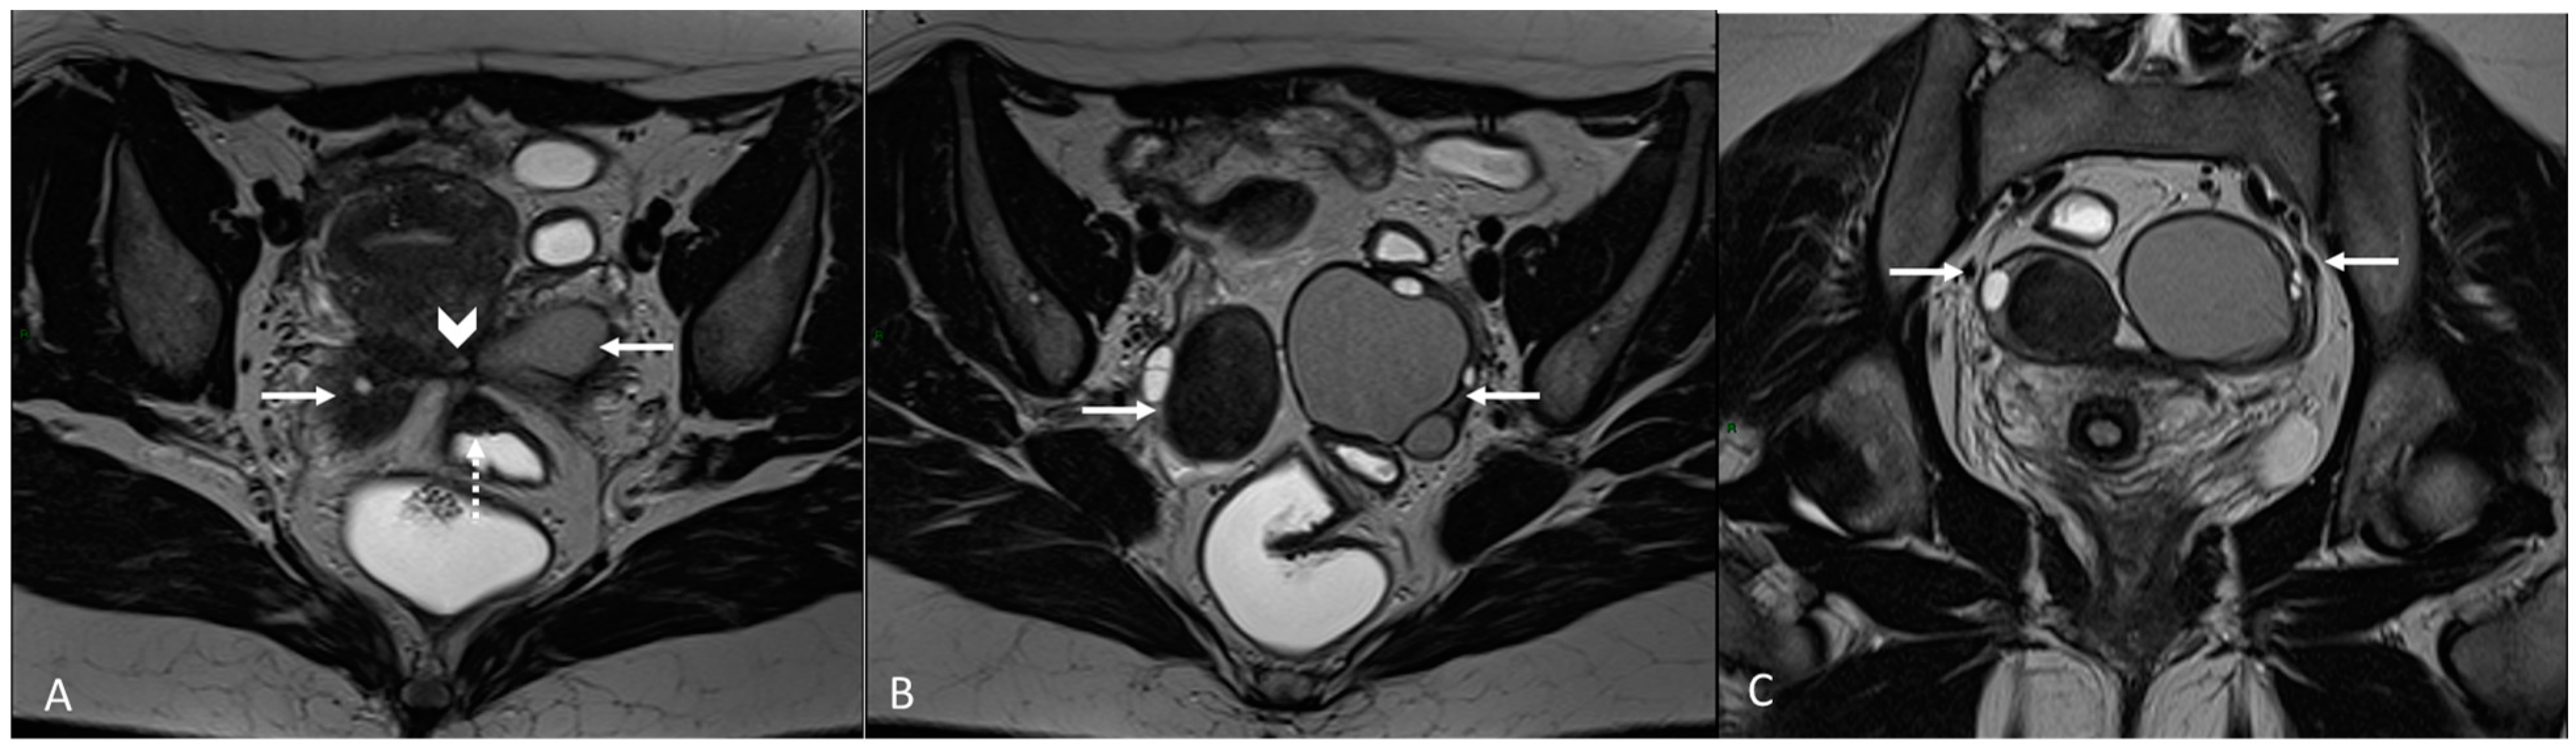

In this paragraph, we will explore the main signs in post-operative imaging in order to provide the radiologist with an indication to evaluate MRIs of women with extensive and complex endometriosis undergoing surgery (Figure 15 and Figure 16).

Figure 15.

Para-uterine fluid collection in a 43-year-old female who underwent several gynecological surgeries for deep infiltrative endometriosis. (A) Axial T2WI. Compartmentalized hyperintense collection in the left para-uterine area after pelvic surgery (white arrow). (B) Coronal T2WI. Endometriotic localization of the vescico-uterine pouch (black arrow).

Figure 16.

Localization of endometriosis in the left parametrium and ureteral stenosis in 49-year-old female who underwent supracervical hysterectomy, bilateral salpingectomy and mild vaginal bleeding and abdominal pain. (A) Axial T2WI; (B) Sagittal T2WI. Endometriotic localization of the left parametrium (white arrow), with irregular margins and heterogeneous signal intensity. Tractions towards the sigmoid colon, left pararectal fascia, anterior pelvic peritoneal reflection and adnexa. Ureteral stenosis caused by the parametrial plaque (dotted arrows in (B)). (C) Axial T2WI; (D) Axial fat-suppressed T1WI. Endometriotic nodule of the left pelvic wall (white arrow).

According to Chamié et al., the first pelvic post-operative MRI should be performed after 6 months. It could be anticipated in selected cases of women who are undergoing medically assisted procreation for infertility [89,90].

One of the main challenges for the radiologist is to make a correct differential diagnosis between post-operative fibrosis and recurring/residual disease.

MRI can highlight the difference between these two conditions: fibrotic scars or plaques appear as bands of hypointensity on T2WI, without areas of cystic degeneration, blood foci (hyperintense in T1WI) or even nodular thickenings that are otherwise typical signs of endometriotic lesions [89].